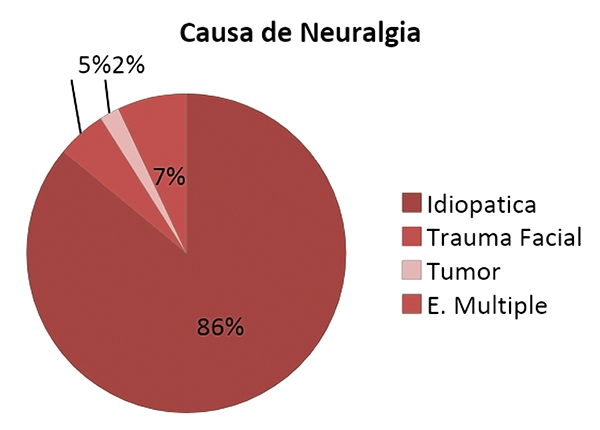

En 51 pacientes la neuralgia trigeminal fue esencial (idiopática sin causa objetivable) (86%), fue posterior a un trauma facial en 3 pacientes (5%), secundaria debida a esclerosis múltiple se observó en 4 procedimientos (7%), 1 paciente fue secundaria a un tumor de glomus yugular inoperable (2%), en 1 paciente fue luego de descompresiva neurovascular por técnica microquirúrgica con recidiva del dolor (graf. 4). Se observó recidiva en 23 procedimientos con una tasa global de 31%.

Gráfico 4: Porcentaje por causa.